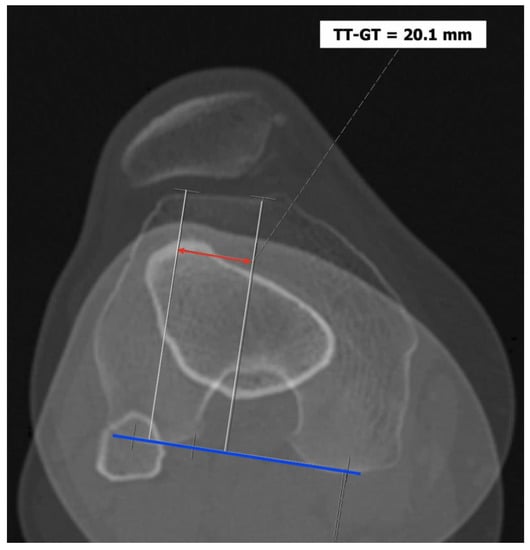

- The tibial tuberosity-trochlear groove (TT-TG) distance [13,14] is defined as the transverse length between the most prominent point of the tibial tuberosity and the trochlear groove on the femur, calculated on axial images (CT scan or MRI), representing the axial malalignment of the extensor mechanism. The greater the distance, the greater the lateralizing force acting on the patella. It is pathological when TT-TG > 13 mm on MRI or TT-TG > 20 mm on a CT scan (Figure 4 and Figure 5).